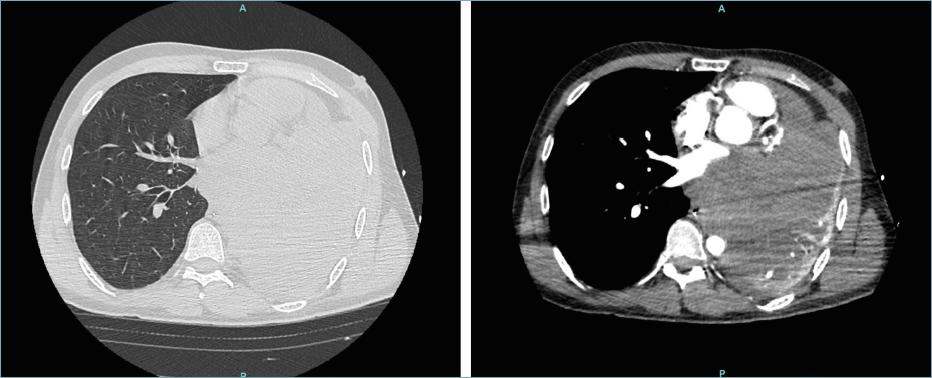

We describe the case of a 27-year-old male, non-smoker, who presented at our institution with hemoptysis. Initially, an infectious disease, such as tuberculosis, was suspected. A computed tomography (CT) showed a voluminous neoformation in the hilum and the left side of the mediastinum, infiltrating the left atrium and encompassing both the aortic arch and the pulmonary artery (Fig. 1).

Figure 1. Computed tomography (CT) scan reveals a voluminous neoformation in the hilum and the left side of the mediastinum infiltrating heart and great vessels.